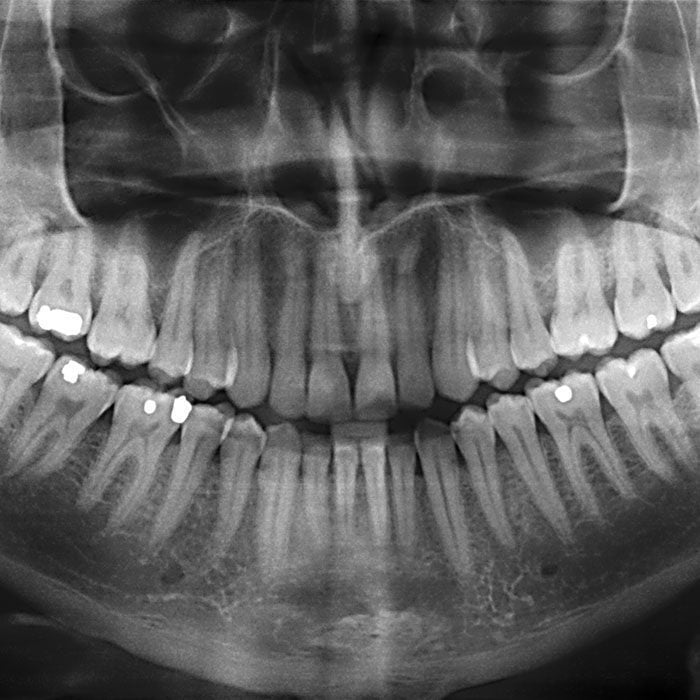

How Does a Tooth Become Infected?

A TOOTH INFECTION is when bacteria invade the pulp at the core of a tooth, whether…